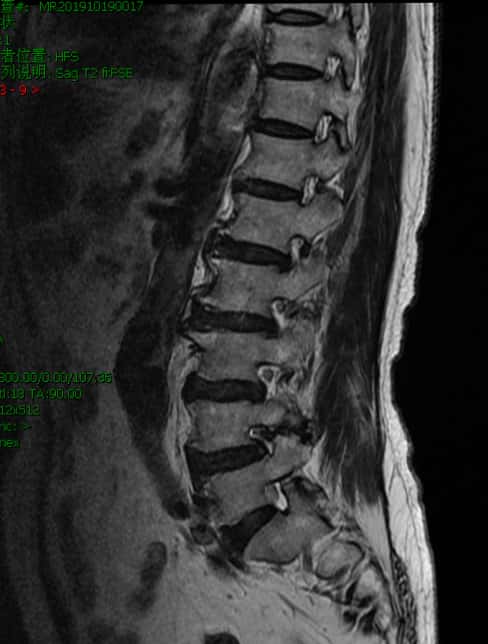

那么再看看患者的CT和MRI。问题并不简单。1997年因腰椎间盘突出,于北京XH医院行腰椎后路手术

核磁上可见椎4/5间孔狭窄,神经根受压变形。

核磁上可见椎间孔狭窄,神经根受压变细。